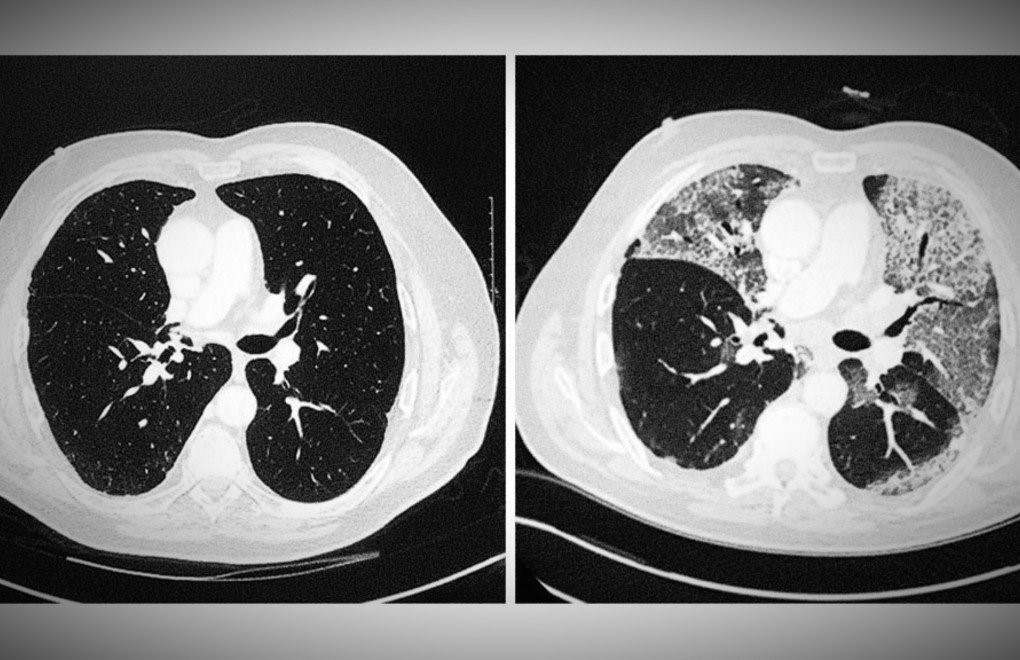

Karşılaştırılan röntgen sonuçları büyük dikkat çekti. En soldaki görselde sigara içen bir bireyin akciğer filmi görülürken sağdaki filmde ise Kovid-19’u yenmiş bir bireyinki bulunuyor.

Akciğer filminde siyah alanlar ne kadar fazla ise o kişinin ciğer kapasitesi ve sağlığı o kadar iyi demektir. Beyaz kısımların artması ise akciğerin kapasitesinin azaldığı anlamını taşır.

Karşılaştırılan röntgen sonuçlarıyla Kovid-19’u geçirmiş ve sağlığına kavuşmuş kişilerin ciğerlerinde görülen hasarın sigara bağımlısı olan kişilerden çok daha kötü olduğunu gözler önüne seren Bankhead-Kendall, ‘Sağlıklı bir bireyin röntgen sonucunda siyah alan büyük olur. Bu da o kişinin ciğerlerine alabileceği oksijen seviyesini gösterir.

Sigara içenlerde hafif hareler yer alırken Covid-19 hastalarının ciğerleri ise bembeyazdır. Yani bu da koronavirüsü yenenlerde bile akciğer sorunları yaşanabildiğini gösteriyor’ açıklamasında bulundu.